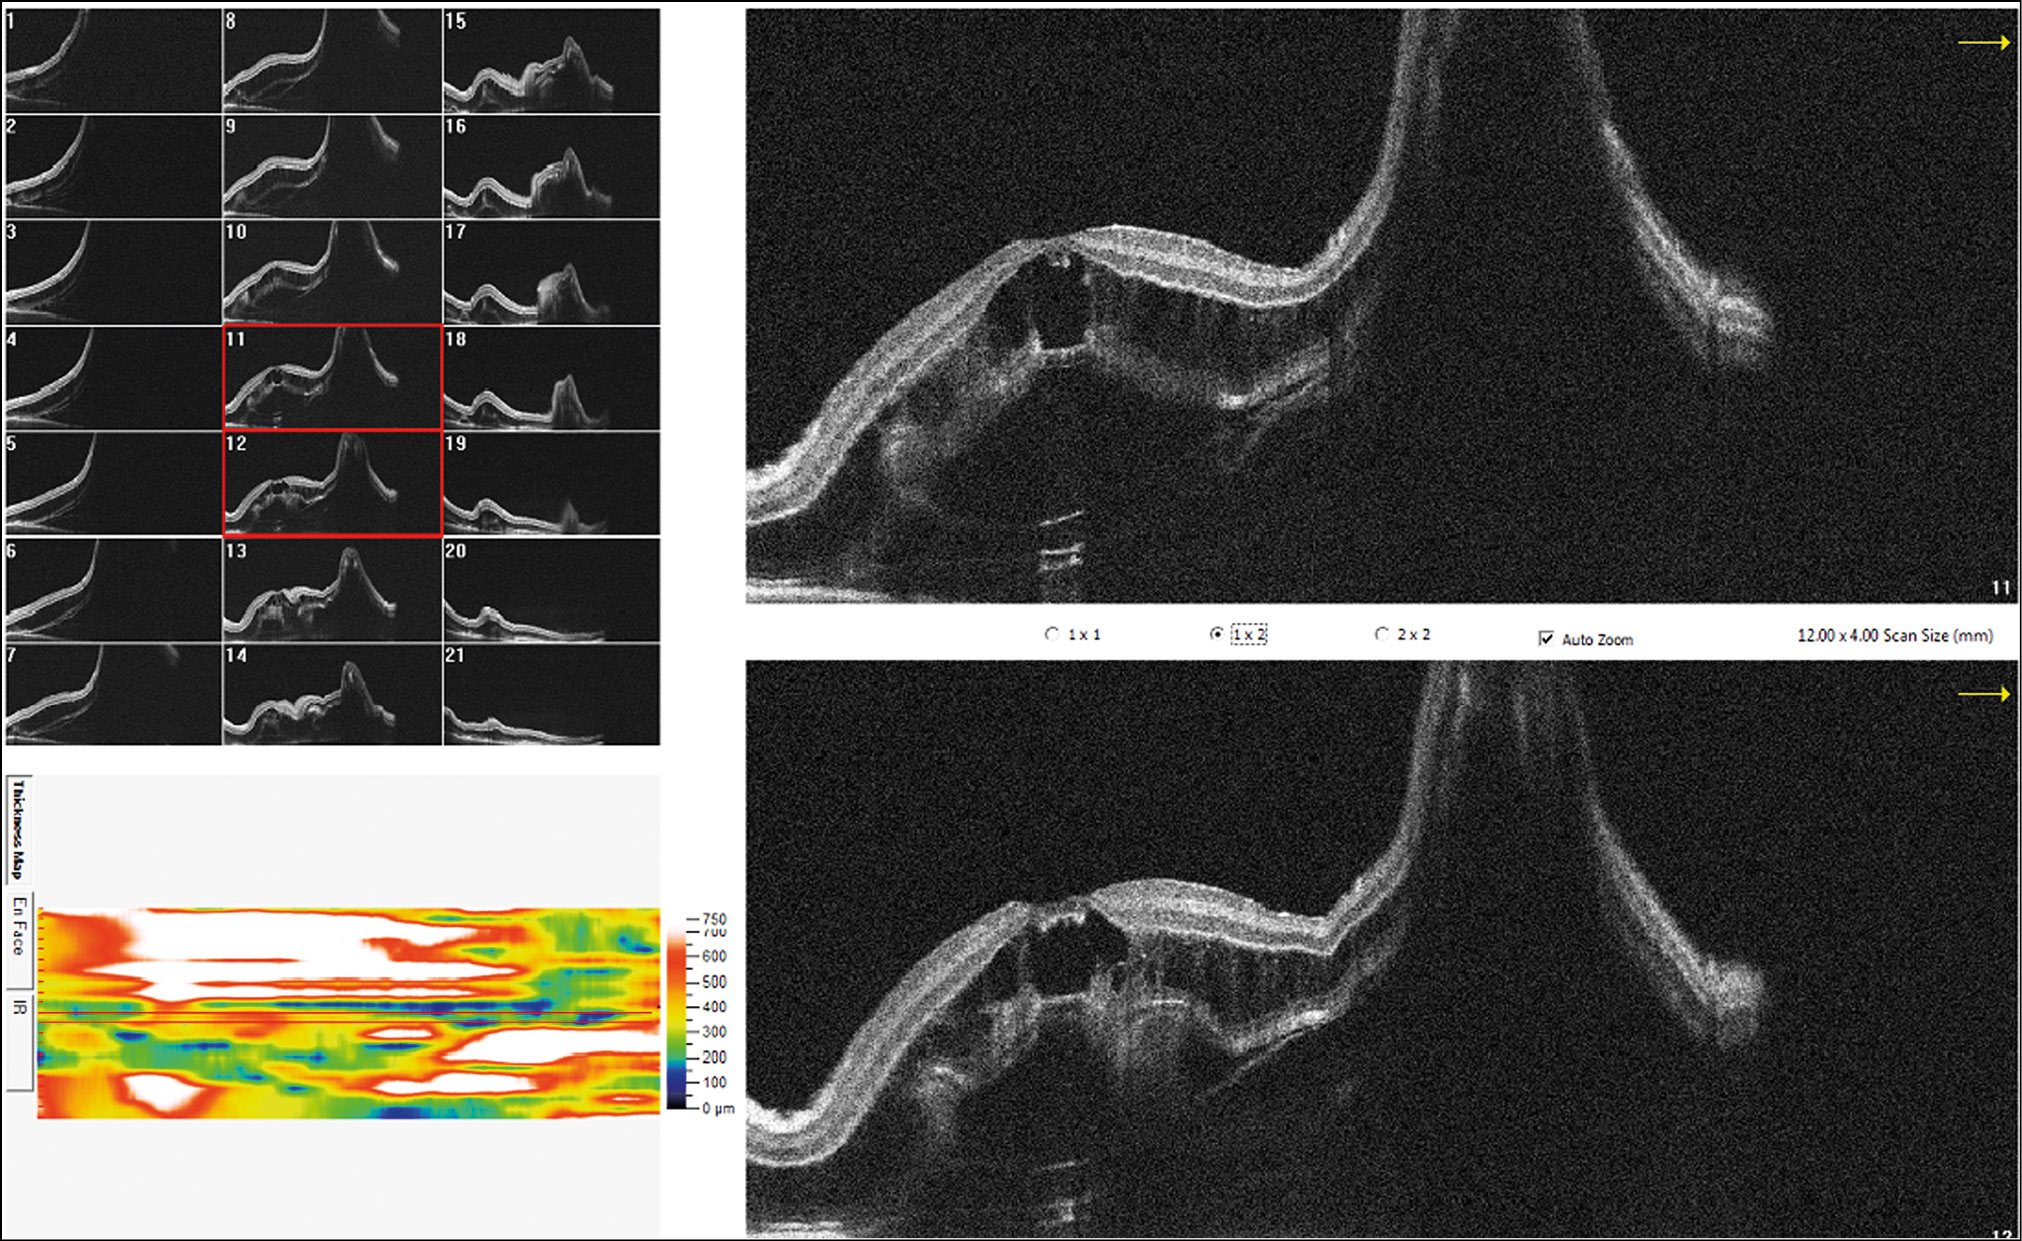

RESULTS: This article presents the clinical case of postoperative choroidal detachment in a child with Sturge–Weber–Crabbe syndrome after microinvasive non-penetrating glaucoma surgery. Against the background of the existing anomalies in the development of an optic disc after antiglaucomatous intervention for decompensated glaucoma, after the normalization of IOP, the patient developed choroid detachment with exudative retinal detachment the next day of operation. After conservative therapy involving bed rest and double instillation of mydriatics for 1 month, the situation was completely resolved and his vision was restored to 1.0.

DISCUSSION: The atypicality of our clinical case of CD lies in the overly pronounced exudative component. In addition to the classic CD vesicles, we observed high exudative retinal detachment as well as high retinoschisis, which is extremely atypical for classical CD. Considering the characteristics of congenital syndrome, it is necessary to accurately differentiate atypical CCA from the rare choroidal effusion syndrome, which also includes CCA with retinal detachment, but does not present with retinoschisis. Against the background of conservative therapy with bed rest and two instillations of mydriatics for 1 month, the situation was completely resolved, and the patient’s vision was restored to 1.0. In the treatment of such patients, it is always necessary to consider their individual anatomical features as well as to understand the detailed pathogenesis of the complications that arise before rushing to repeat surgery.